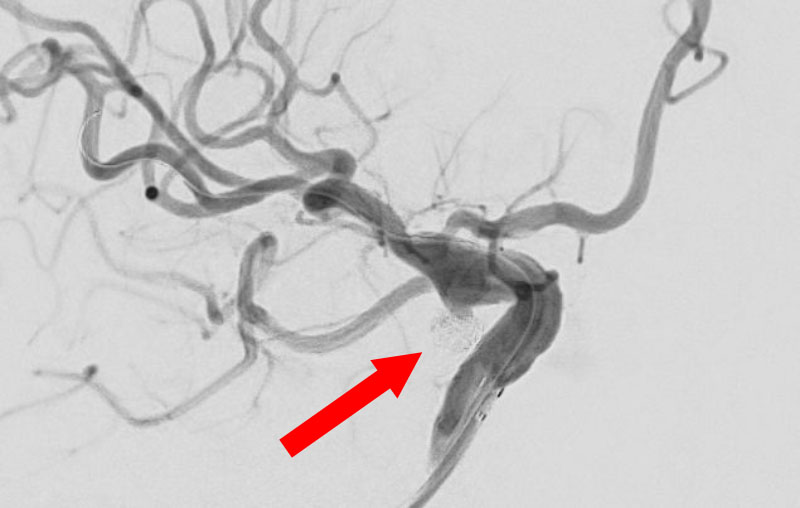

No.1631 手術中